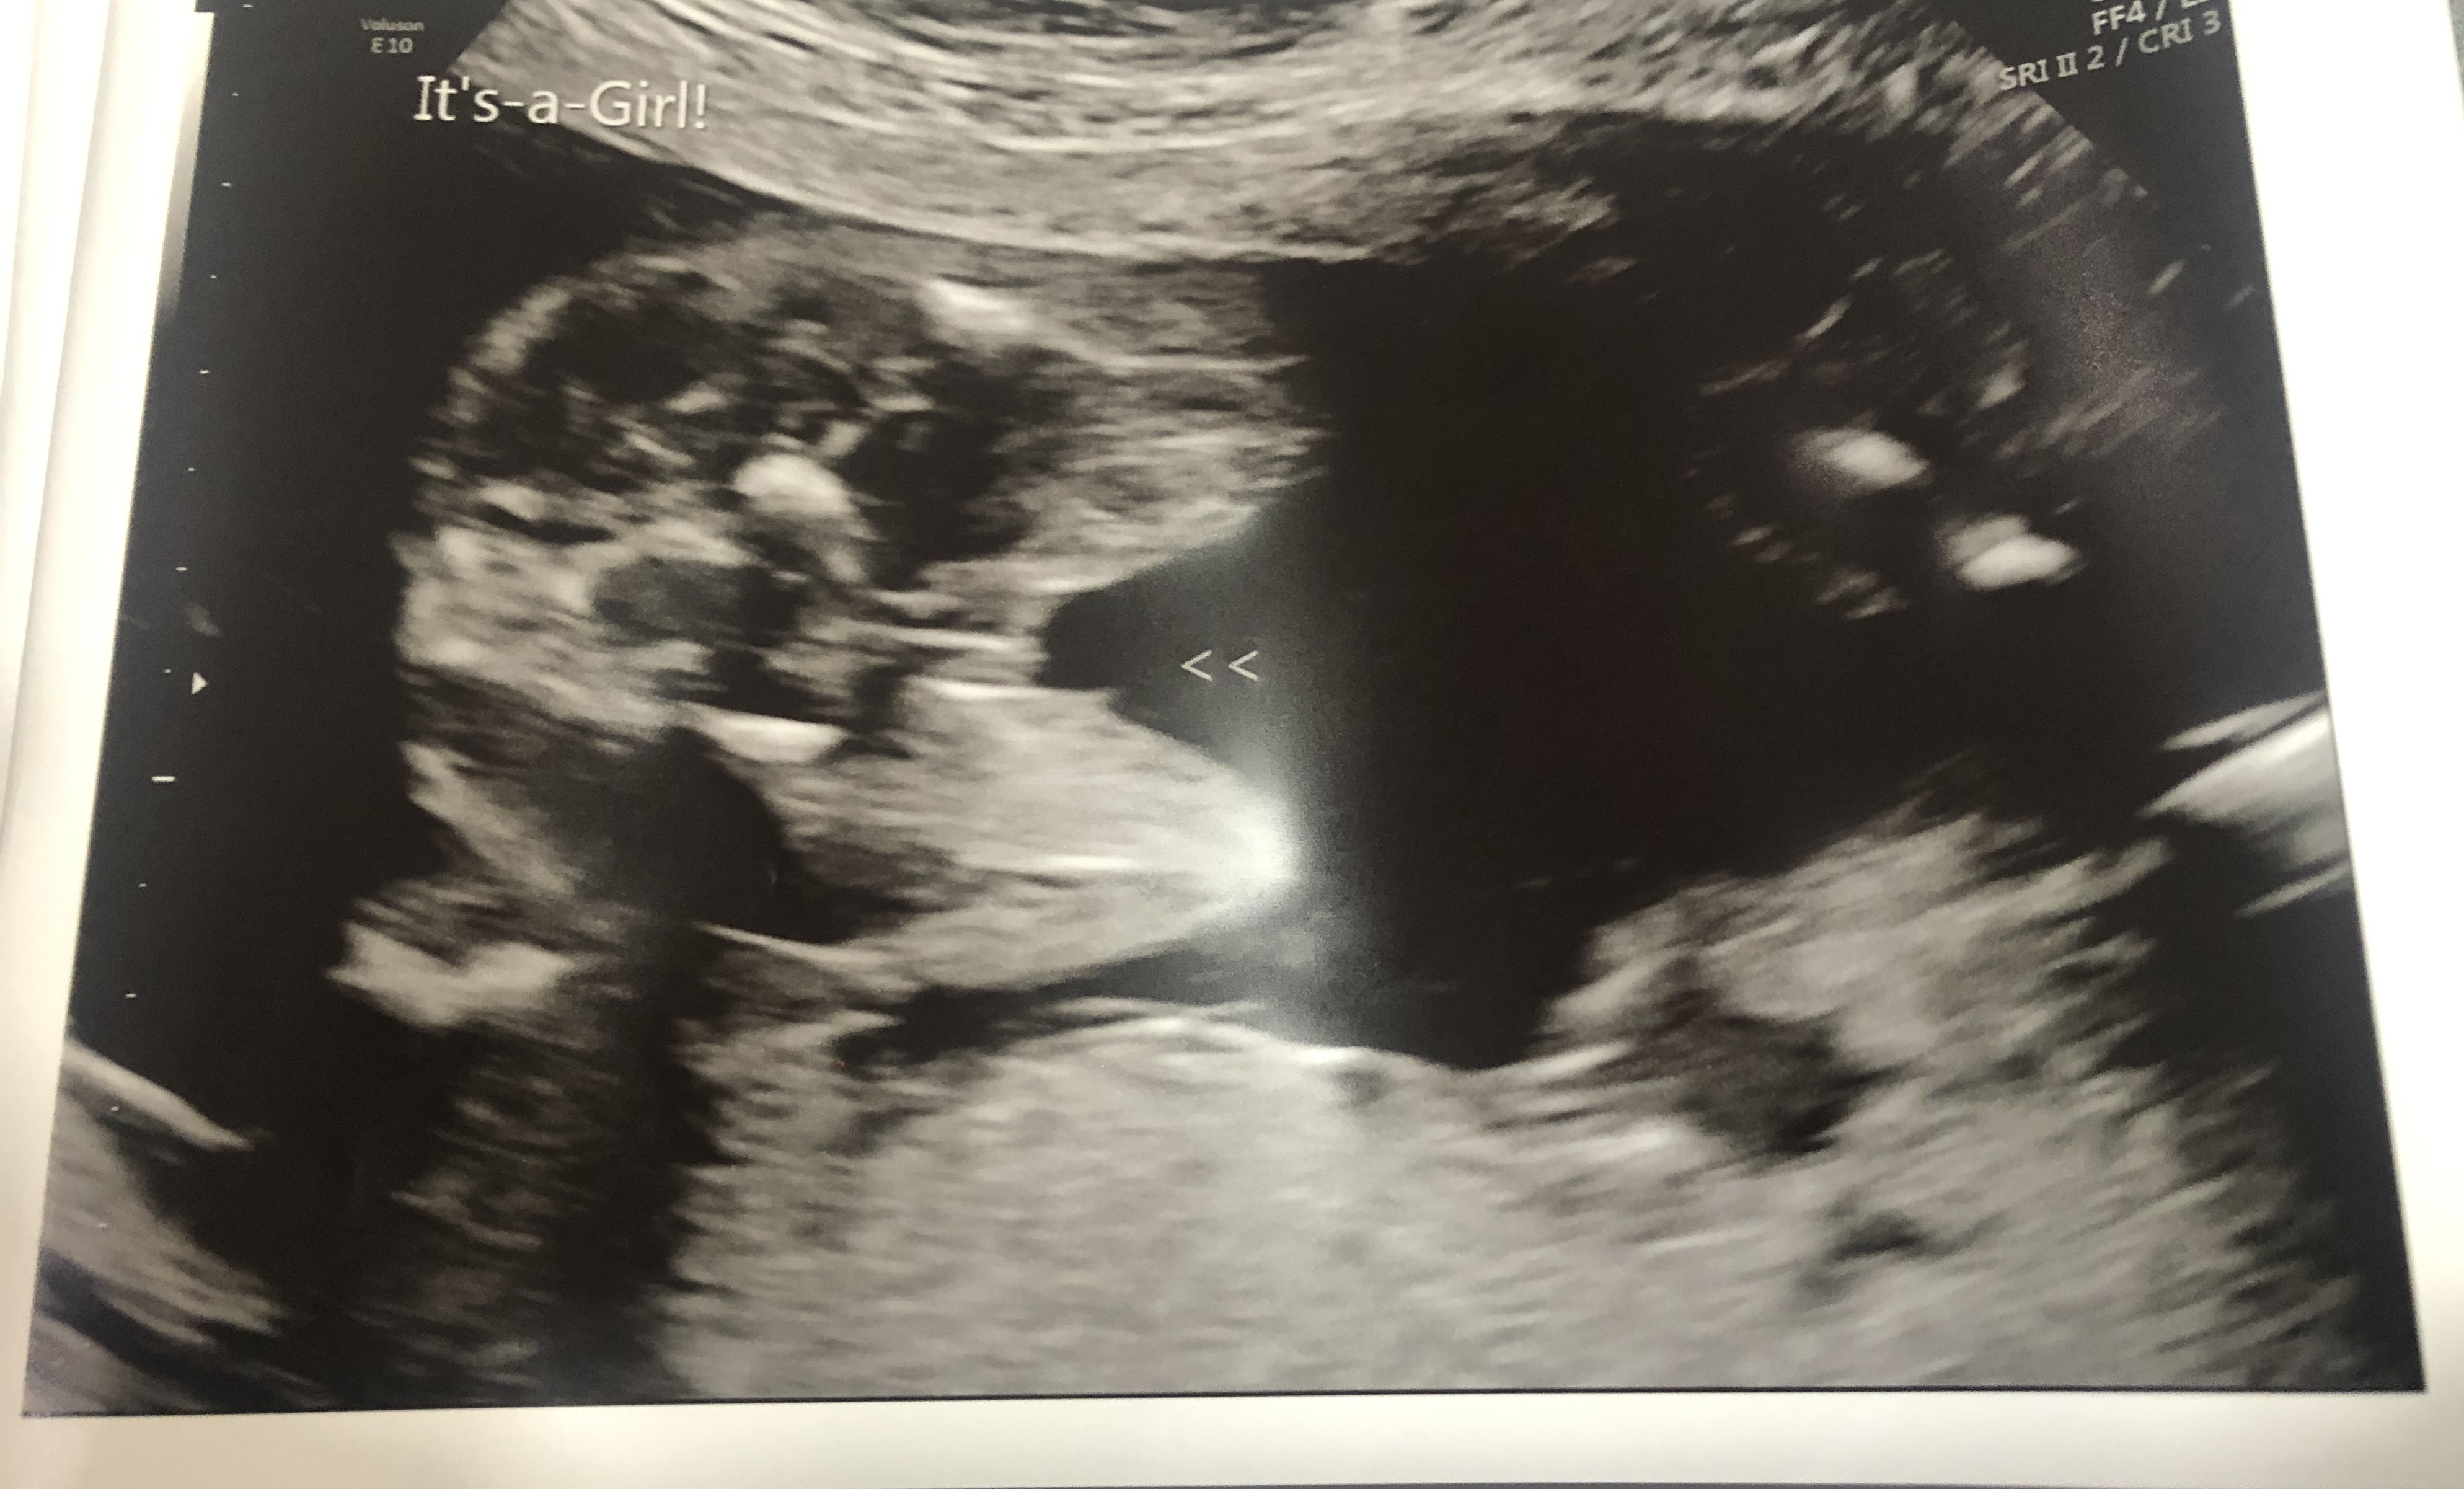

Here’s our (third) girl. We are so excited! ❤️

Evelyn grace. 20 weeks! So excited for our third baby girl

20 week ultrasound ❤️❤️